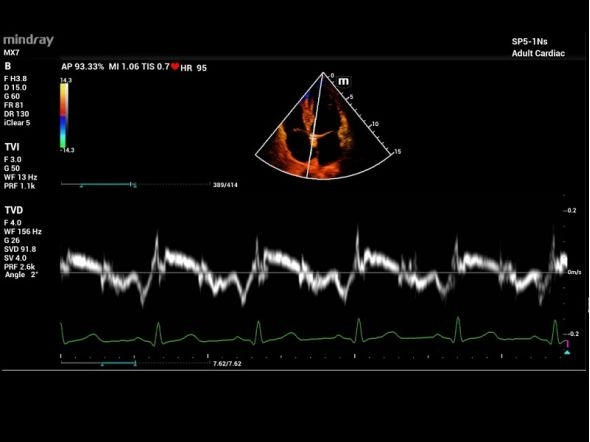

Tissue Doppler Imaging(TDI)

- Несколько режимов тканевого доплера TDI: TVI, TEI, TVD и TVM

- Поддержка сравнительного анализа в реальном времени и в автономном режиме

Исследование сердца взрослого TDI